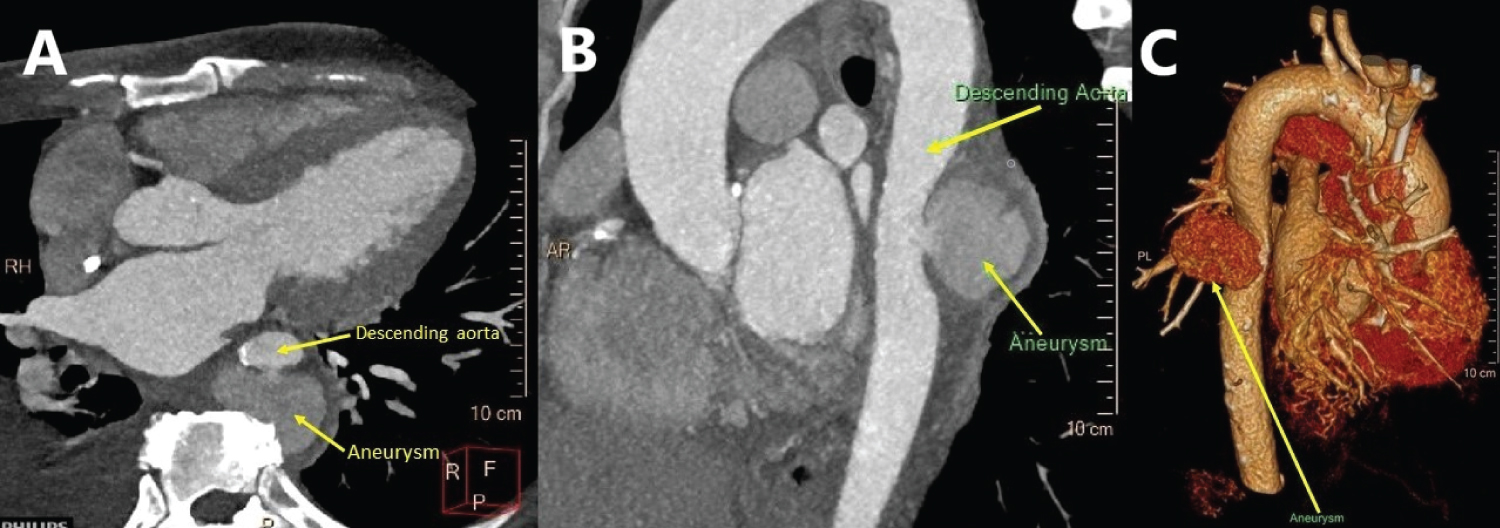

50-year-old woman with end-stage renal failure on haemodialysis presented with chest pain. She was recently treated with methicillin-resistant Staphylococcus aureus bacteraemia secondary to tunnel line infection. Transthoracic echocardiogram demonstrated a linear structure in the descending thoracic aorta suspicion for an aortic dissection (Figure 1). Computed tomography (CT) thoracic aorta (Figure 2) showed a large descending thoracic aortic aneurysmat the T7/T8 level. Because of her comorbidities, a stent was deployed in view of high risk of perforation and she was placed on prolonged antibiotics.Post-stenting CT scan (Figure 3) a few weeks later showed a patent stent and the aneurysm appeared successfully excluded.

Figure 2: (A & B) CT thoracic aorta shows a descending thoracic aortic aneurysm (up to 5.6 cm maximum transverse diameter in the axial plane) at the T7/T8 level; (C) Volume rendered image of the CT thoracic aorta demonstrating a large aortic aneurysm (arrow).